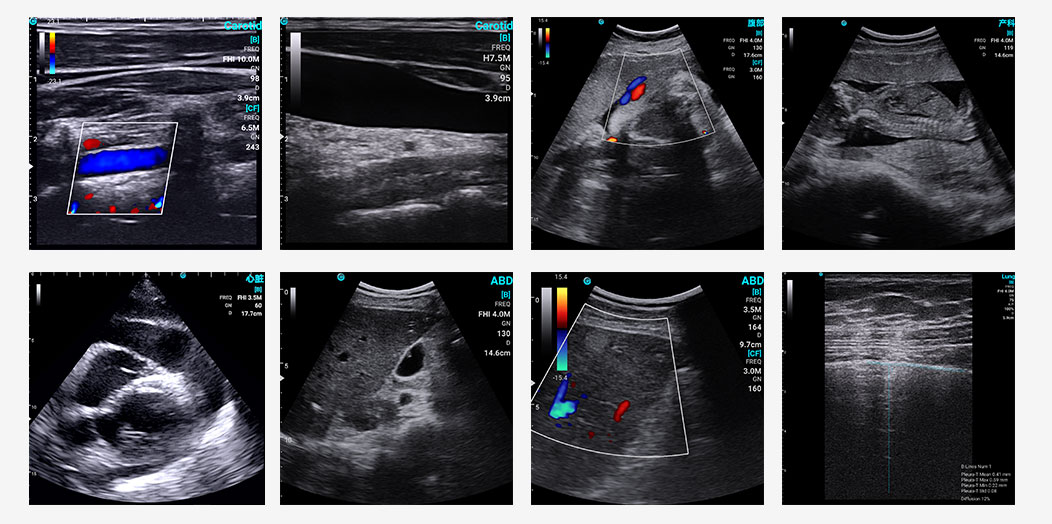

Exemplary sonographic images of SonoEye

SonoEye stood out in B-mode image quality, ranking among the top performers. This is a key factor in its success in clinical applications, as high resolution and optimal contrast are vital for accurate diagnoses.